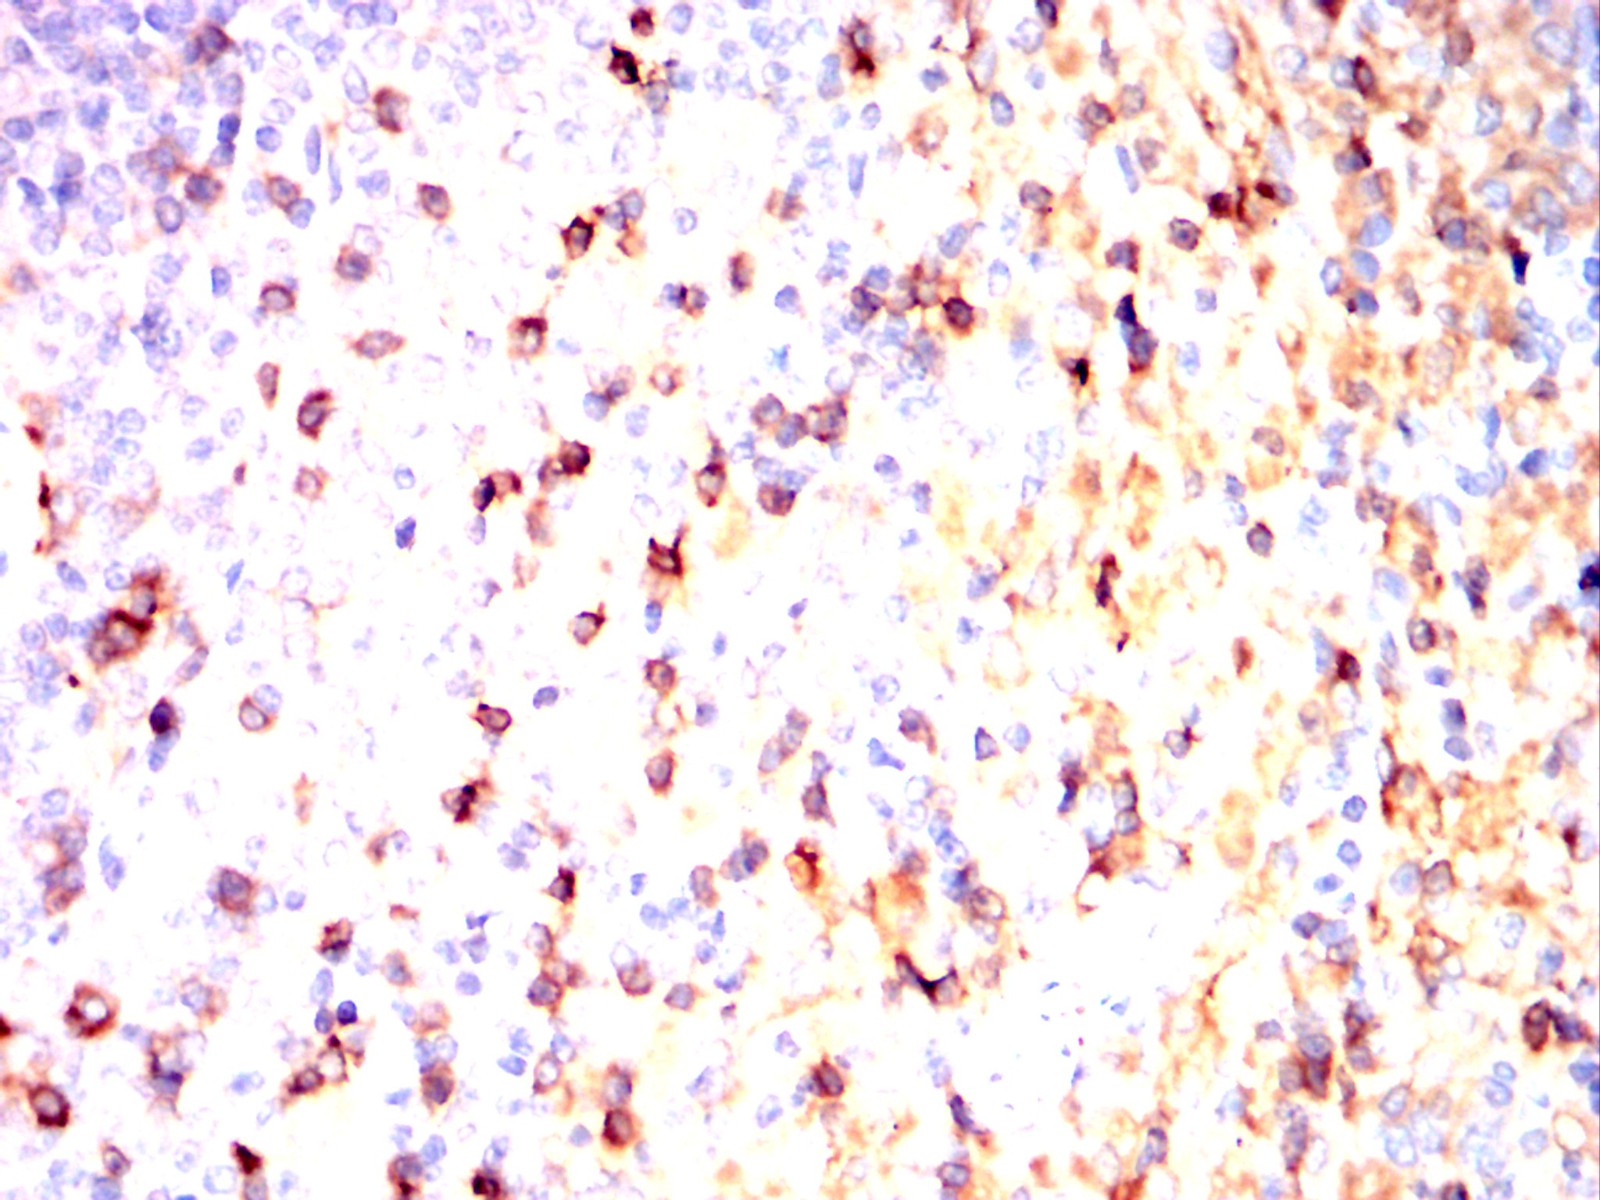

Immunohistochemical analysis of paraffin-embedded Rat spleen using AVP mouse mAb with DAB staining